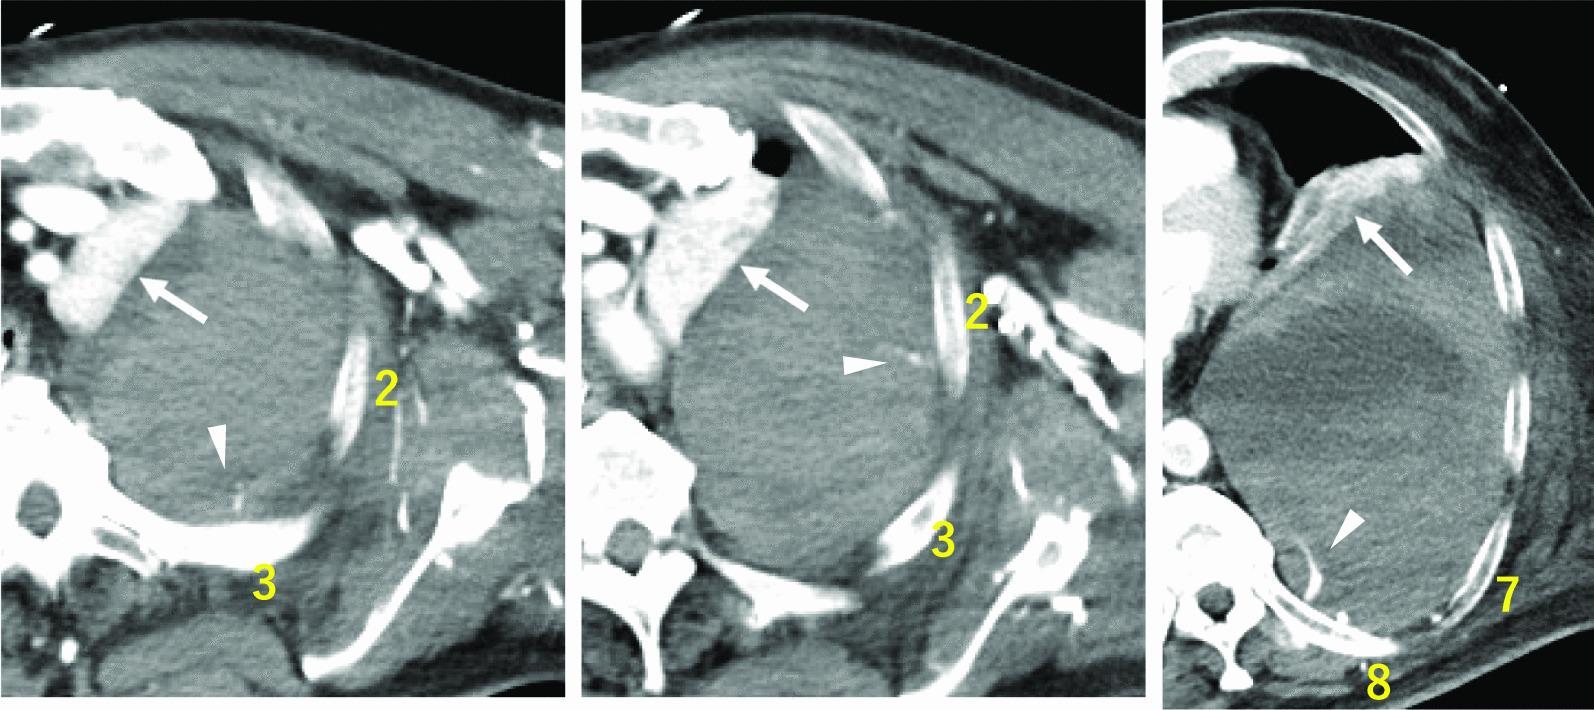

A 63-year-old Japanese man was admitted to the emergency department owing to sudden chest and back pain, dizziness, and nausea. Emergency coronary angiography revealed myocardial infarction secondary to right coronary artery occlusion. After intra-aortic balloon pumping, percutaneous coronary intervention was performed in the right coronary artery. At 12 hours following percutaneous coronary intervention, the patient developed new-onset left anterior chest pain and hypotension. Contrast-enhanced computed tomography revealed 15 sites of contrast extravasation within a massive left extrapleural hematoma. Emergency angiography revealed contrast leakage in the left 6th to 11th intercostal arteries; hence, transcatheter arterial embolization was performed. At 2 days after transcatheter arterial embolization, his blood pressure subsequently decreased, and contrast-enhanced computed tomography revealed the re-enlargement of extrapleural hematoma with multiple sites of contrast extravasation. Emergency surgery was performed owing to persistent bleeding. No active arterial hemorrhage was observed intraoperatively. Bleeding was observed in various areas of the chest wall, and an oxidized cellulose membrane was applied following ablation and hemostasis. The postoperative course was uneventful.

一名 63 岁的日本男性因突发胸痛、背痛、头晕和恶心而被收入急诊部。紧急冠状动脉造影显示右冠状动脉闭塞引起的心肌梗死。在主动脉内球囊泵后,对右冠状动脉进行了经皮冠状动脉介入治疗。在经皮冠状动脉介入治疗后 12 小时,患者出现新发左前胸疼痛和低血压。增强 CT 显示巨大左胸外血肿内有 15 个造影剂外渗部位。紧急血管造影显示左第 6 至 11 肋间动脉有造影剂渗漏;因此,进行了经导管动脉栓塞术。在经导管动脉栓塞术后 2 天,他的血压随后下降,增强 CT 显示胸外血肿再次扩大,有多个造影剂外渗部位。由于持续出血,进行了紧急手术。术中未观察到活跃的动脉出血。在胸腔壁的各个部位观察到出血,并在消融和止血后应用氧化纤维素膜。术后过程平稳。